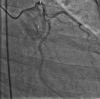

Figure 3

Angiographic picture showing left sinus of Valsalva aneurysm rupturing into right atrium. 1, Left coronary sinus aneurysm; 2, fistulous tract between aneurysmal sac and right atrium; 3, ruptured sinus of Valsalva aneurysm opening into right atrium; 4, right coronary artery.